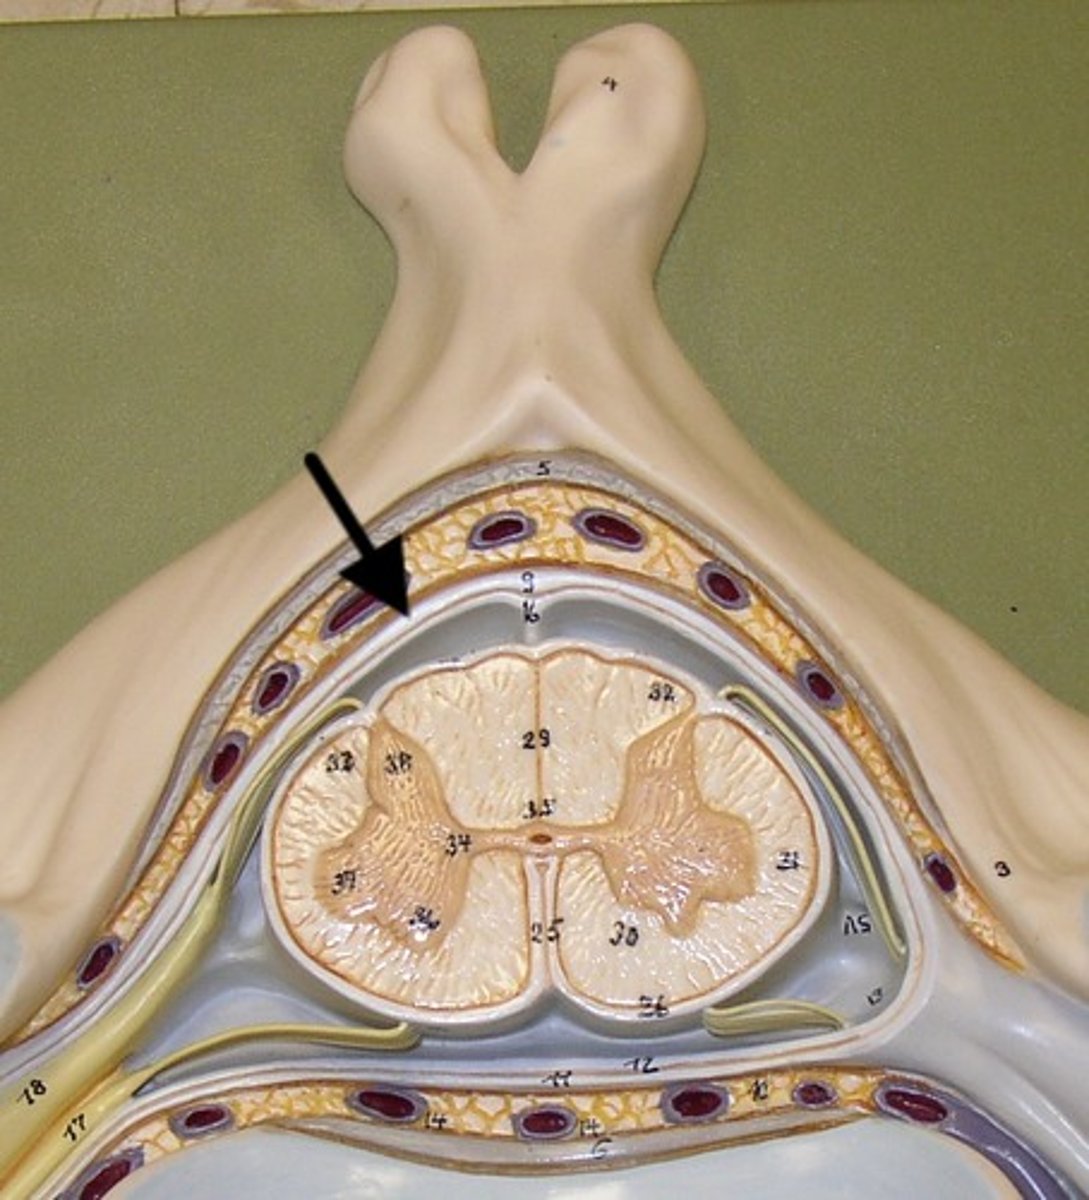

spinal meninges

3 specialized membranes surrounding spinal cord and brain

Stability, shock absorption, carry blood supply (oxygen and nutrients)

3 spinal meninges (Superficial to deep)

dura mater, arachnoid mater, pia mater

Dura mater

tough outer layer of the meninges

arachnoid mater

Made of simple squamous epithelium

Pia mater

thin, delicate inner membrane of the meninges

subarachnoid space

between arachnoid mater and pia mater

filled with cerebrospinal fluid

shock absorber; diffusion of gases, nutrients, etc.

blood vessels for spinal cord

epidural space

space between dura mater and vertebrae

denticulate ligaments

pia mater, through the arachnoid mater, to dura mater

Prevents lateral movement

Lumbar puncture

Withdrawal of cerebrospinal fluid

needle inserted into subarachnoid space between two lumbar vertebrae.

Also known as spinal tap